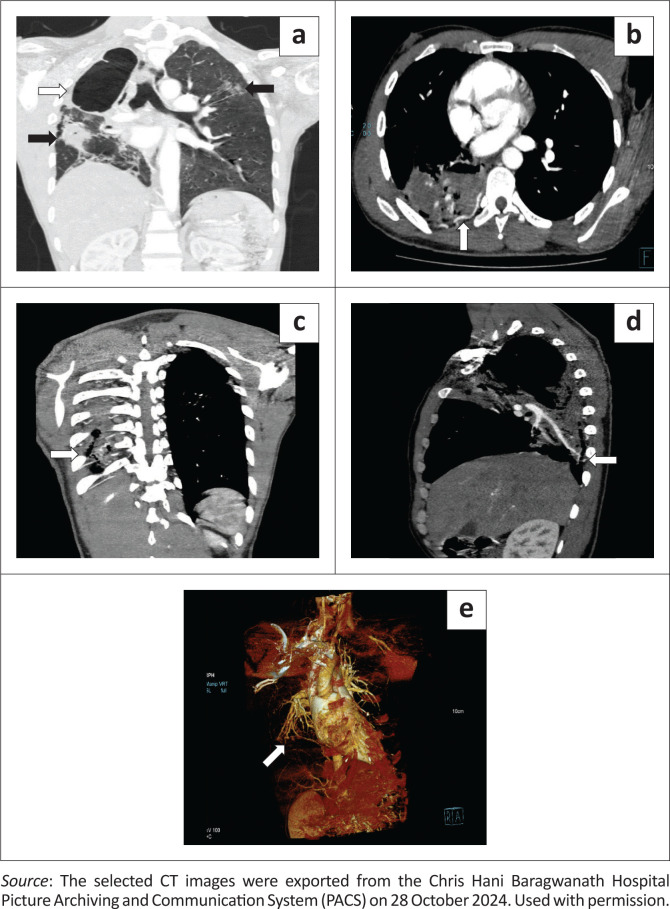

Intercostal artery-to-pulmonary artery fistula is an extremely rare variant of systemic artery-to-pulmonary artery fistulas (SA-PAFs). A case of a 38-year-old man presenting with clinically significant haemoptysis secondary to an intercostal artery-to-pulmonary artery fistula in the setting of post-pulmonary tuberculosis (TB) bronchiectasis is described. The fistulae were successfully treated with endovascular coils.

Contribution: This case report illustrates an intercostal artery-to-pulmonary artery fistula associated with post-primary tuberculosis bronchiectasis, highlighting its multimodal radiological features and successful endovascular treatment.